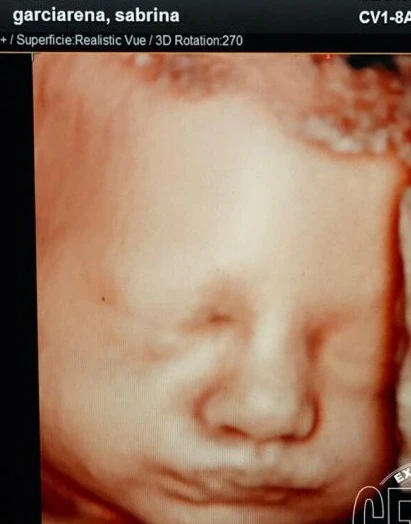

Una de las últimas ecografías que se realizó la actriz fue con tecnología 4D y pudo ver la carita de la niña en camino. ¿A quién se parece?